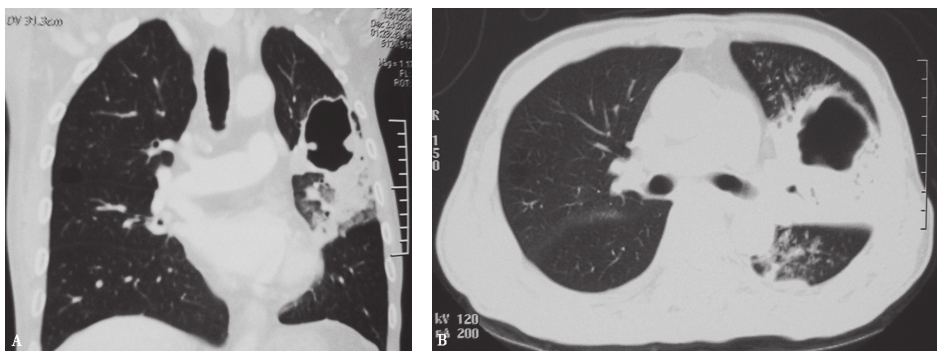

由于结核分枝杆菌增殖缓慢,需要16~18小时分裂一次,病理检查往往可见渗出、变性和增殖3种病理类型同时存在。成年人肺内结核病均为继发性肺结核,绝大多呈慢性和亚急性经过。临床表现为急性病理过程的肺结核主要是血行播散型肺结核(急性粟粒型肺结核)和干酪性肺炎两种类型。前者可出现急性发热,普通抗感染治疗无效,肺内出现密度、大小和分布“三均匀”的粟粒性结节,可发展为ARDS;后者的病变多局限于一个或多个叶段,影像学表现为实变或沿气道播散病灶,大多可见树芽征,有时也会出现肺内空洞(表现为无壁、薄壁和厚壁空洞)(图16),但罕有肺内脓性改变和空洞内脓性液平。

图16 肺结核伴空洞胸部CT表现

男性患者,72岁,发热、咳嗽2个月,诊断为肺结核伴空洞